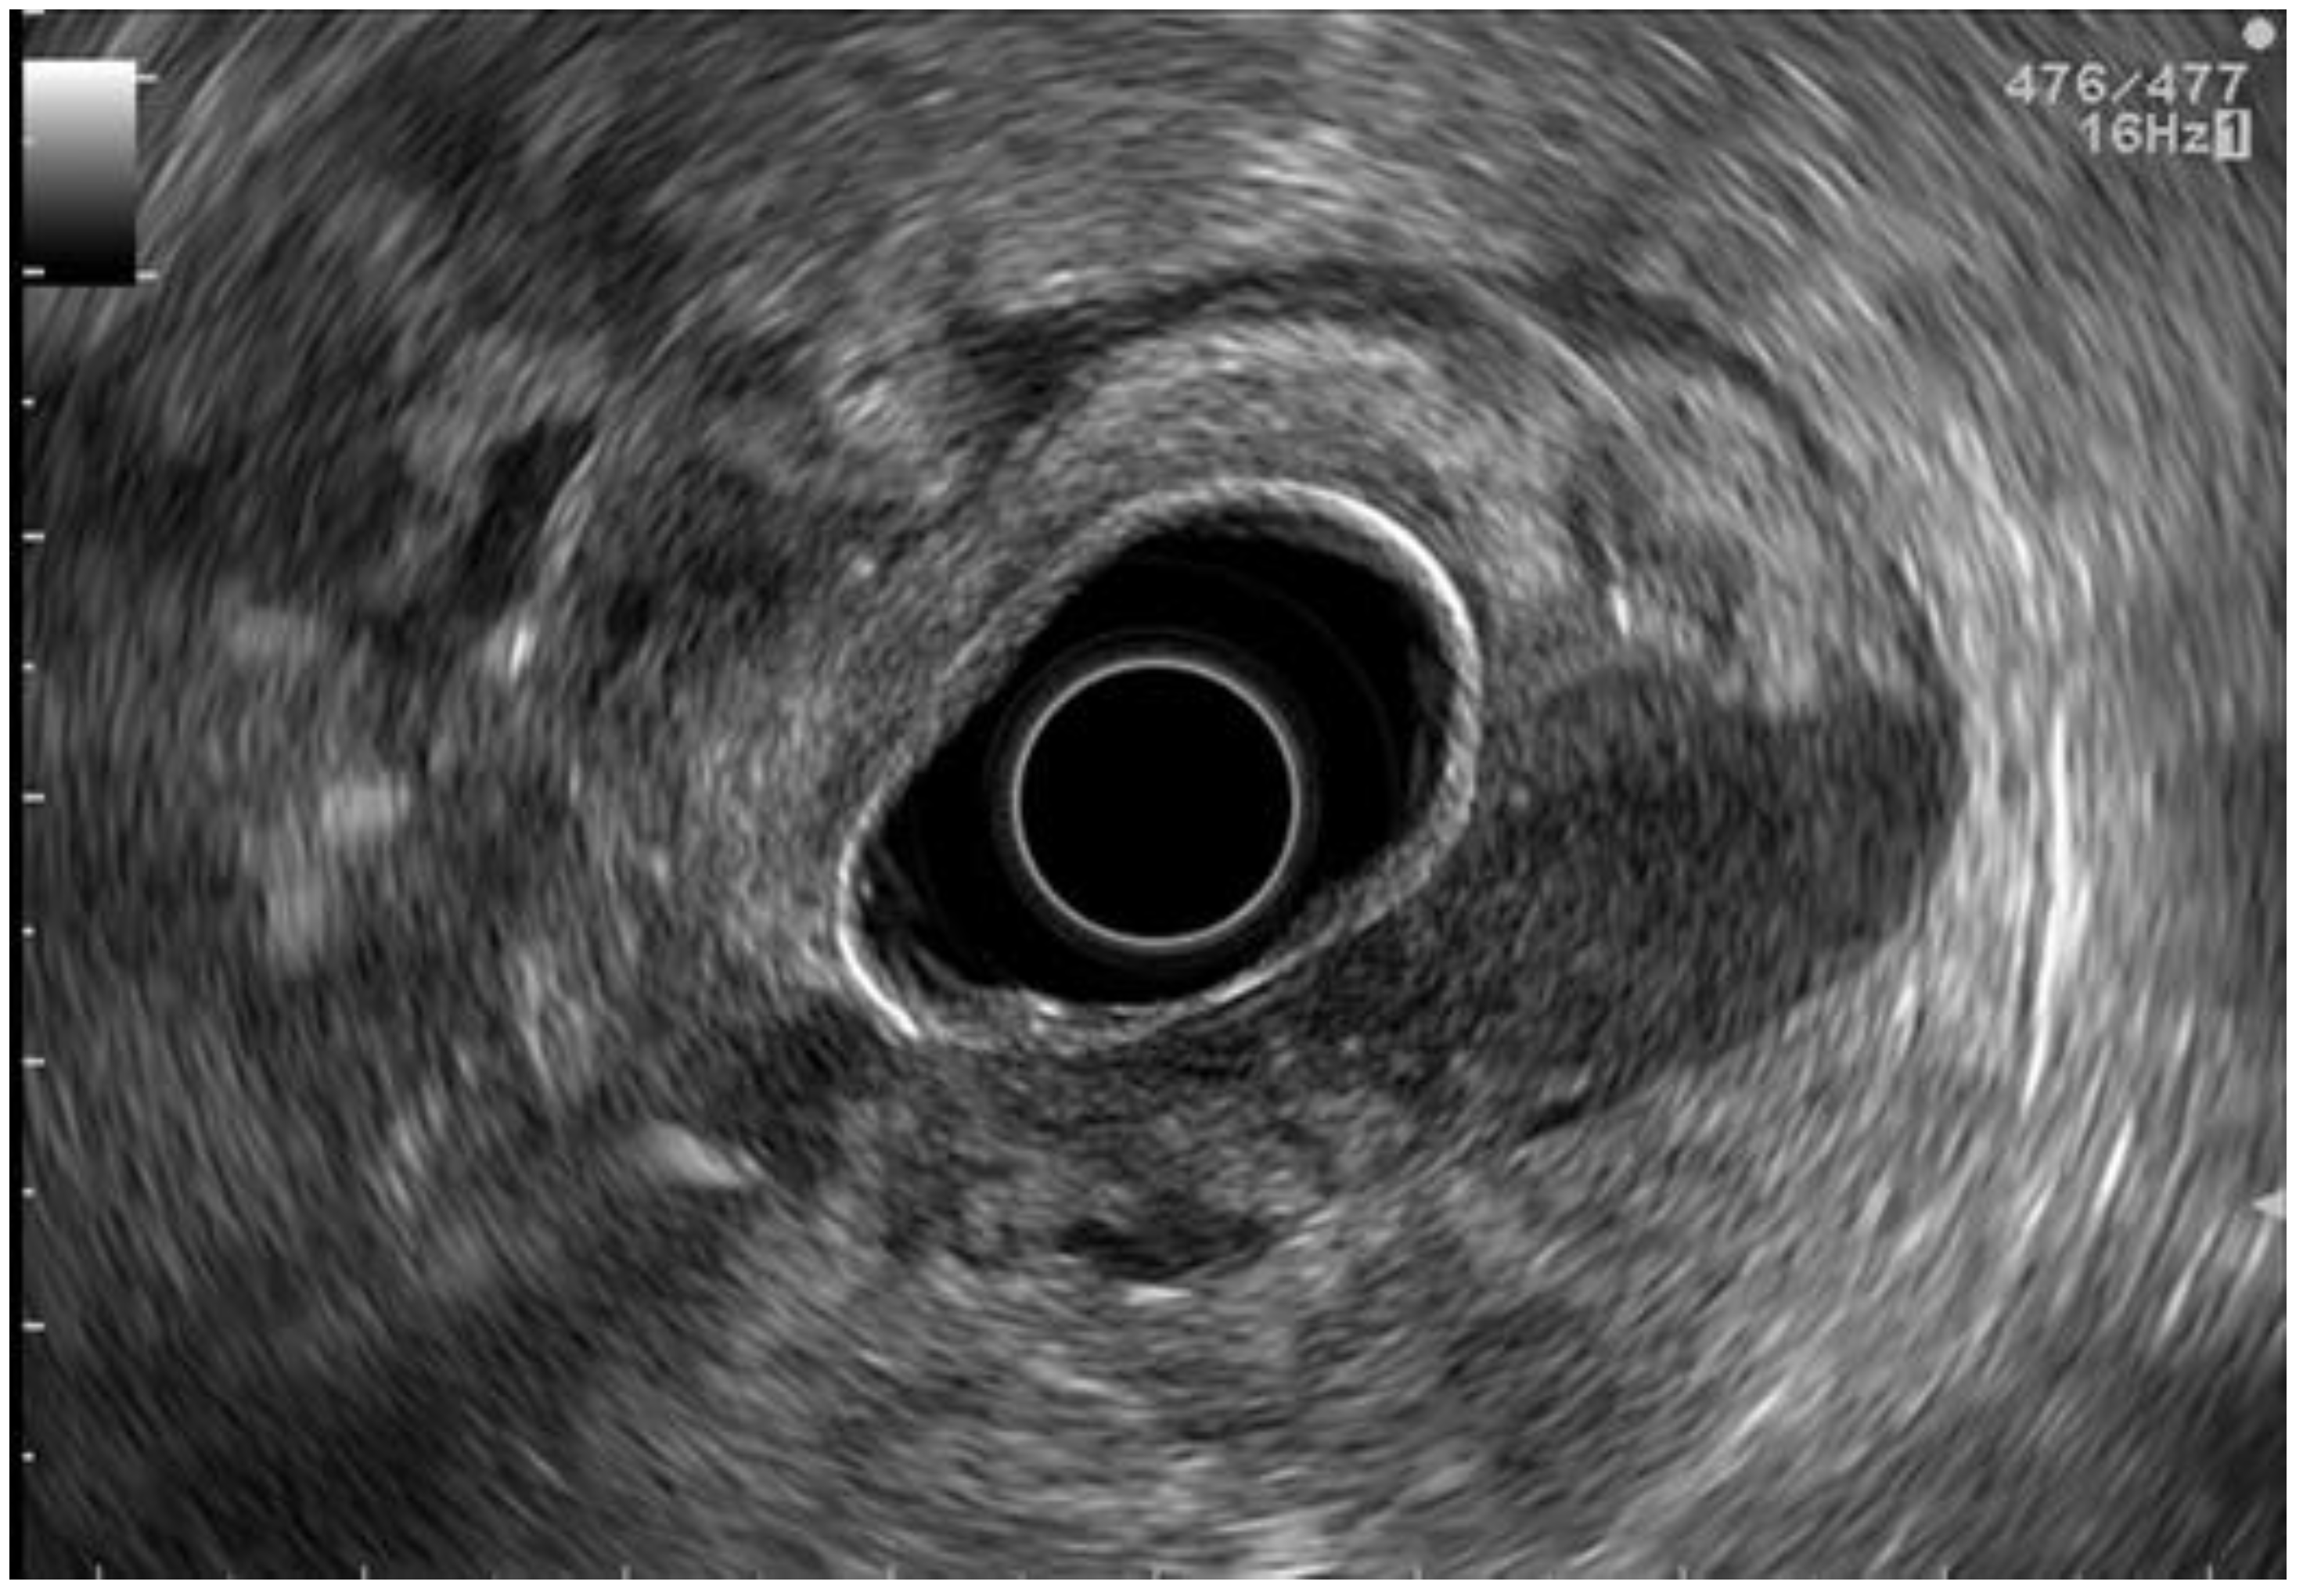

2.3. EUS Staging

2.4. PET-CT Staging